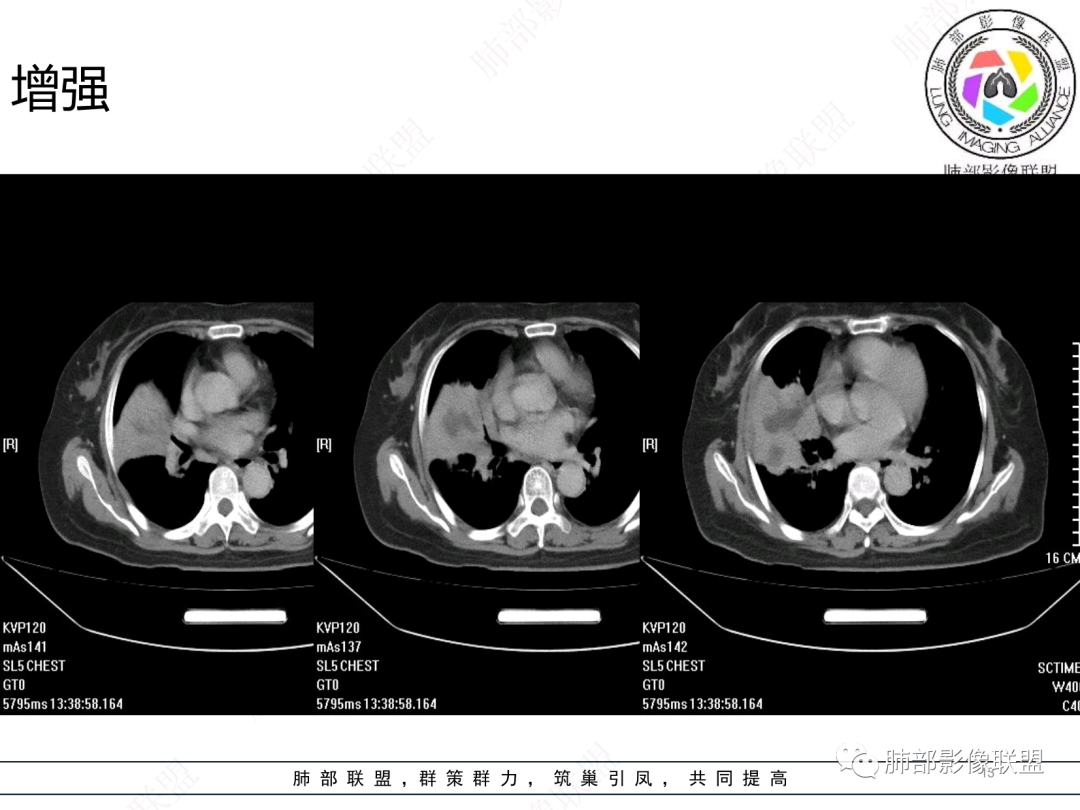

女,74岁,咳嗽咳痰加重一周入院,右肺中叶大片实变影,边界清晰,病灶内密度不均匀,右肺中叶支气管变窄,增强扫描病灶明显强化,考虑恶性病变能,鉴别肺脓肿。

胸部CT:右肺中下叶大片实变影,界清,边缘膨隆为主,中叶外侧段支气管截断。增强不均匀强化,边缘可见血管影迂曲模糊,内见条带状低密度影。治疗后病变进展。考虑恶性,鳞Ca?鉴别TB、OP。

老年女性,慢性病史,炎性指标稍高,肿标正常,右中下肺大片实变,跨叶生长,边界清,收缩力差,膨隆生长为主,支气管杵状截断,均匀强化,其内坏死边界清,可见悬浮气泡,整体观察,病灶膨隆生长为主,邻近肺野无播散灶,形态单一,尽管慢性病史,影像不支持OP和TB,支气管截断呈杵状,肿标正常,均匀强化,虽是高龄患者,诊断恶性肿瘤有点牵强,综和分析,首选炎性病变放线菌感染,其次考虑低度恶性占位炎机母。

南边:跨叶、楔形/边缘平直、支气管壁无破坏/连续/局部无膨大、实变区肺动脉走形自然、实性部分均匀、延迟强化、坏死腔内壁光滑/内壁强化环/近端与支气管相通,这些点均支持炎性。所以综合分析:符合炎性。